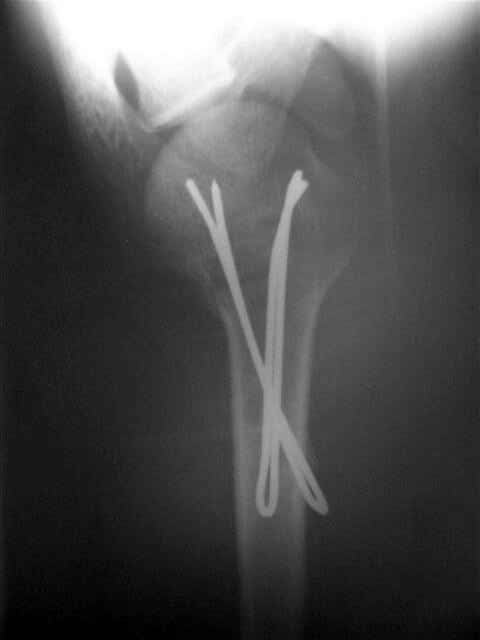

Посылаю послеоперационные Рг граммы.

Я и сам доволен результатом. В предпоследнем письме я кратко описал ход операции - закрыто репонировать не удалось( 2 недели с момента травмы и 1 неделя после неудачной репозиции) после удаления пучков спиц, пришлось сделать - 2см разрез на уровне перелома и с помощью периостального элеватора (золотое правило механики) *одеть* головку на дистальный отломок.

Спицы проводил через старые отверстия, вращая пучок импактором- направителем при его введении в головку.

Женя, привет. Все правильно - молодец. По моему у тебя в презентации должен быть слайд с набором инструментов. Несколько советов - ушко должно быть больше 6 мм - около 8 мм в диаметре, перед введением спиц мы разводим концы - как бы заряжая пружину, вводим конца в канал с помощью риноскопа, но после введения дбиваем спицы через кондуктор для шейки бедра, который имеет внутренний диаметр 10 мм. Всего наилучшего! ЛАФ.